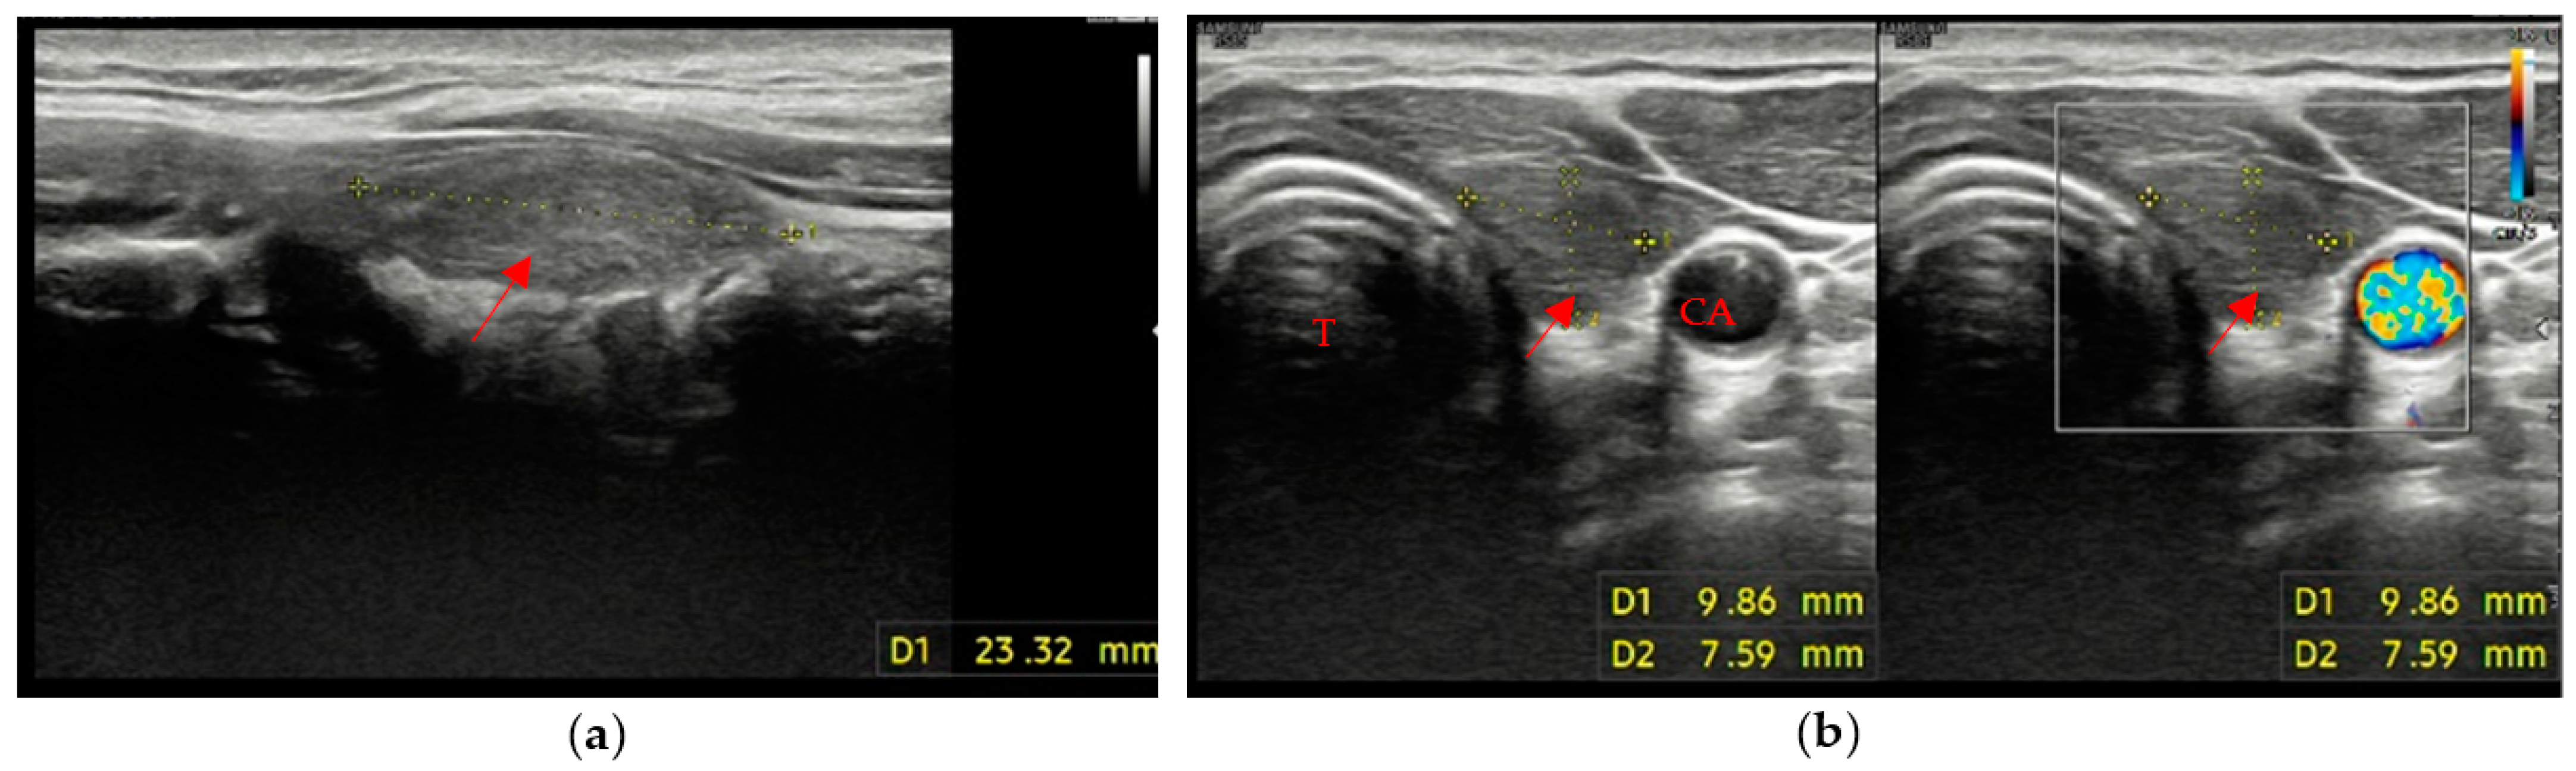

The remaining 3 patients (8% of patients with evidence of residual swab) showed different patterns, with different combinations of margins and ecogenicity. In our experience, we have also found different swab shapes, but the most common are ovoid or pseudo-ovoid shapes; these are the most frequent and most “thyroid-like” shape, and are caused when the remnant has completely obliterated the thyroid space that reproduces the native thyroid gland shape. This form is often associated with the mildly hypoechoic pattern with ill-defined margins (Figure 3a,b).

Data in the literature concerning the biocompatibility, the tolerability and the time resorption of these hemostatic agents are few [22,23,24,25,26]. Our study showed a longer resorption time than the data provided by the producers (7–14 days with regard to the oxidized and regenerated cellulose-based hemostatic; the failure rate for absorption is not clearly specified by the manufacturers). Therefore, it is important to keep in mind that failure or delay in the reabsorption of the hemostatic material can cause diagnostic mistakes that affect the patient’s therapeutic path. In fact, some of the patients had already undergone further diagnostic investigations before being enrolled in the study, such as scintigraphy and ultrasound-guided needle aspiration for residual material in the thyroid space in order to exclude a neoplastic recurrence. In particular, seven of these patients were subjected to strict ultrasound surveillance (three-month follow-up), one patient to MRI and three patients to scintigraphic evaluation that showed no areas of significant radiopertechnetate uptake and was negative for residual thyroid tissue in the anatomical loggia (Figure 5a–f). One of the last three patients had also undergone a needle aspiration evaluation that confirmed the presence of the hemostatic, described by the pathologist as “amorphous inorganic material referable to surgical sponge” (a similar case is described by Kurian E.M. et al., in which the patient, during follow-up after lung resection for carcinoma, underwent endobronchial ultrasound-guided transbronchial needle aspiration on suspicion of lymph node metastasis, but the cytological examination showed the presence of foreign material, later proven to be the Surgicel® placed during surgery) [27,28]. Lastly, in two other patients, although they were not subjected to further diagnostic investigations, the presence of the swab was misinterpreted as post-surgical native thyroid residue. These examples make it clear how diagnostic mistakes cause unpleasant consequences for the patient’s diagnostic–therapeutic path and increase the clinical management cost.

Figure 3. “Thyroid-like” shape of the swab (red arrow) in a right hemithyroidectomy (the native gland, pointed out by a red star, is still visible on the left). Trachea (T). (a) Axial view; (b) Longitudinal view.